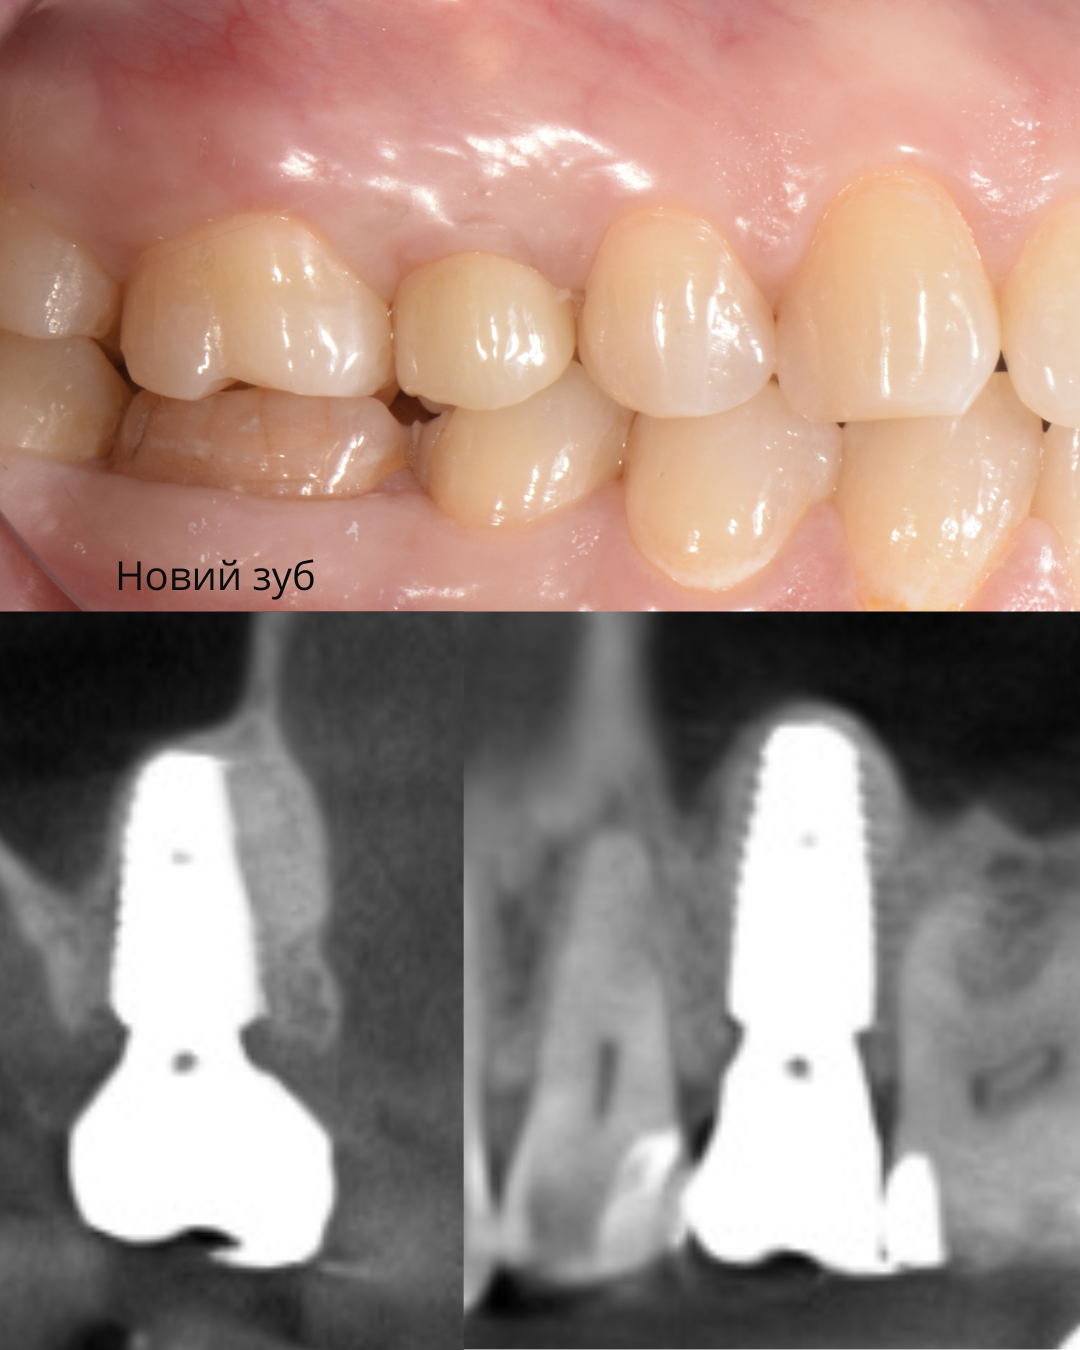

Навігаційна імплантація з кістковою та м'якотканинною пластикою

Жінка, 42 роки

Відсутність жувального зуба на нижній щелепі, виражена атрофія кісткової та м'яких тканин, порушення жувальної функції та естетики.